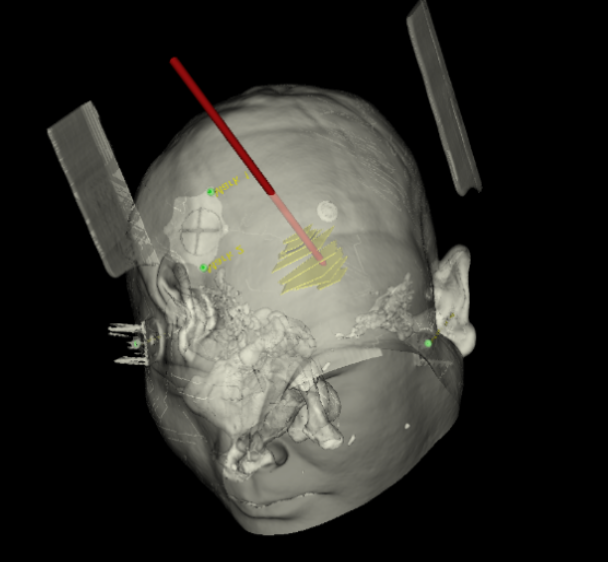

手術(shù)日當(dāng)天,醫(yī)生團(tuán)隊(duì)通過(guò)手術(shù)計(jì)劃系統(tǒng)為患者制定手術(shù)靶點(diǎn)及最安全的入顱路徑,隨后將手術(shù)規(guī)劃導(dǎo)入手術(shù)室的機(jī)器人當(dāng)中。

實(shí)際手術(shù)時(shí),機(jī)器人在幾分鐘內(nèi)就完成了空間注冊(cè),機(jī)械臂在定位儀的引導(dǎo)下自動(dòng)定位,準(zhǔn)確鎖定靶點(diǎn)。

術(shù)前韓帥醫(yī)生使用“睿米”制定手術(shù)規(guī)劃

手術(shù)規(guī)劃在機(jī)器人軟件上制定完成